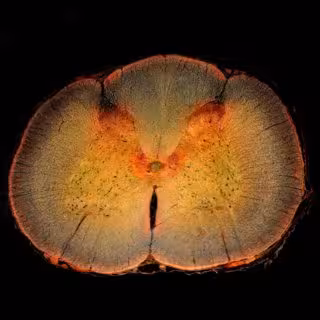

Sección transversal de la médula espinal, incluido el cuerno dorsal de la médula espinal, donde se procesa el dolor.

Para conocer los mecanismos subyacentes a los ritmos de dolor normal y neuropático, los científicos, cuyo trabajo ha sido publicado en la revista 'PLOS Computational Biology', han desarrollado un modelo matemático que simula cómo se transmite el dolor de un nervio al cuerno dorsal de la médula espinal, donde el dolor se procesa inicialmente.